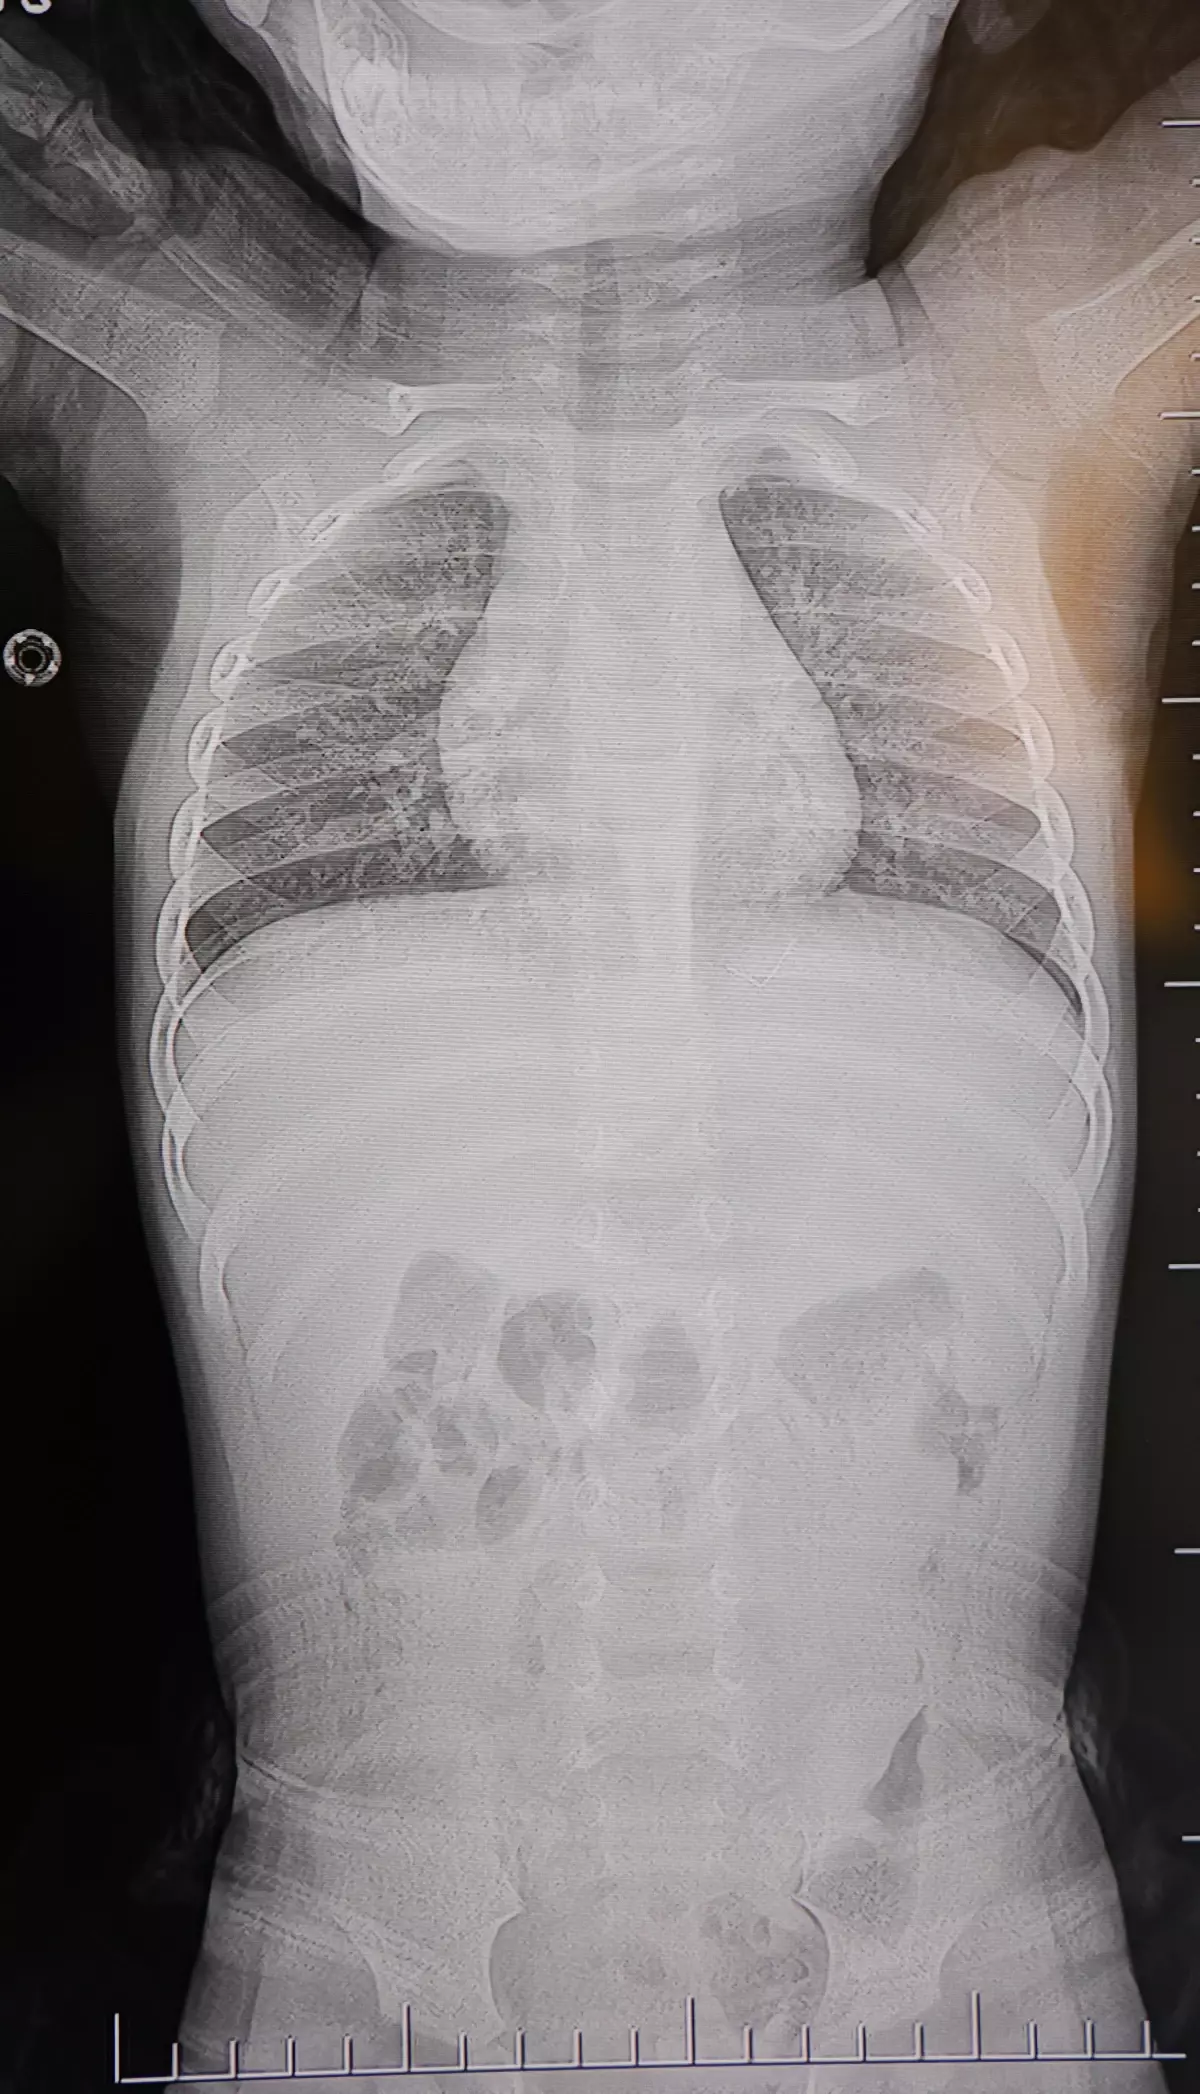

Ailenin son olarak başvurduğu hastanede yapılan tetkiklerde, yabancı cismin cilt altında, omurilik kanalına yakın bir bölgede olduğu ve akciğer zarına doğru ilerlediği belirlendi.

Hasta, genel anesteziye alınmadan, lokal anestezi ve sedasyon eşliğinde ameliyata alındı. Yapılan müdahalede yabancı cisim tamamen çıkarıldı. Çıkarılan cismin, ince zımba teline benzer metal bir tel olduğu ve yaklaşık 2 santimetre uzunluğunda bulunduğu tespit edildi. Hasta, aynı gün taburcu edildi.

Konuya ilişkin açıklama yapan Beyin ve Sinir Cerrahisi Uzmanı Prof. Dr. İdris Altun, "Sırtında yabancı bir cisim olduğu söylenmiş ancak çıkarılamayacağı ve 8 yaşına kadar beklenmesi gerektiği ifade edilmişti. Bize başvurduğunda yaptığımız tetkiklerde, cilt altında, omurilik kanalına çok yakın ve akciğer zarına doğru ilerleyen bir yabancı cisim tespit ettik. Hastamızı tamamen uyutmadan, lokal anestezi ve sedasyon eşliğinde müdahale ederek lezyonu tamamen çıkardık. Çıkardığımız cismin ince zımba teline benzer, yaklaşık 2 santimetre uzunluğunda metal bir tel olduğunu gördük. Bu yabancı cisim alınmasaydı, bölgede enfeksiyon gelişebilirdi. Enfeksiyon sonucu omurilik kanalında ciddi hasarlar oluşabilir, çocuk büyüdükçe cismin hareket etmesine bağlı olarak omurilikte zedelenmeler meydana gelebilirdi. Ayrıca yana doğru ilerleyerek akciğer zarına ve akciğere batma riski vardı. Bu da enfeksiyona ve ilerleyen süreçte tümörle karışabilecek tablolara neden olabilirdi. Şu an hastamız gayet sağlıklı. Gerekli kontrolleri yaptık ve aynı gün taburcu ettik" dedi.